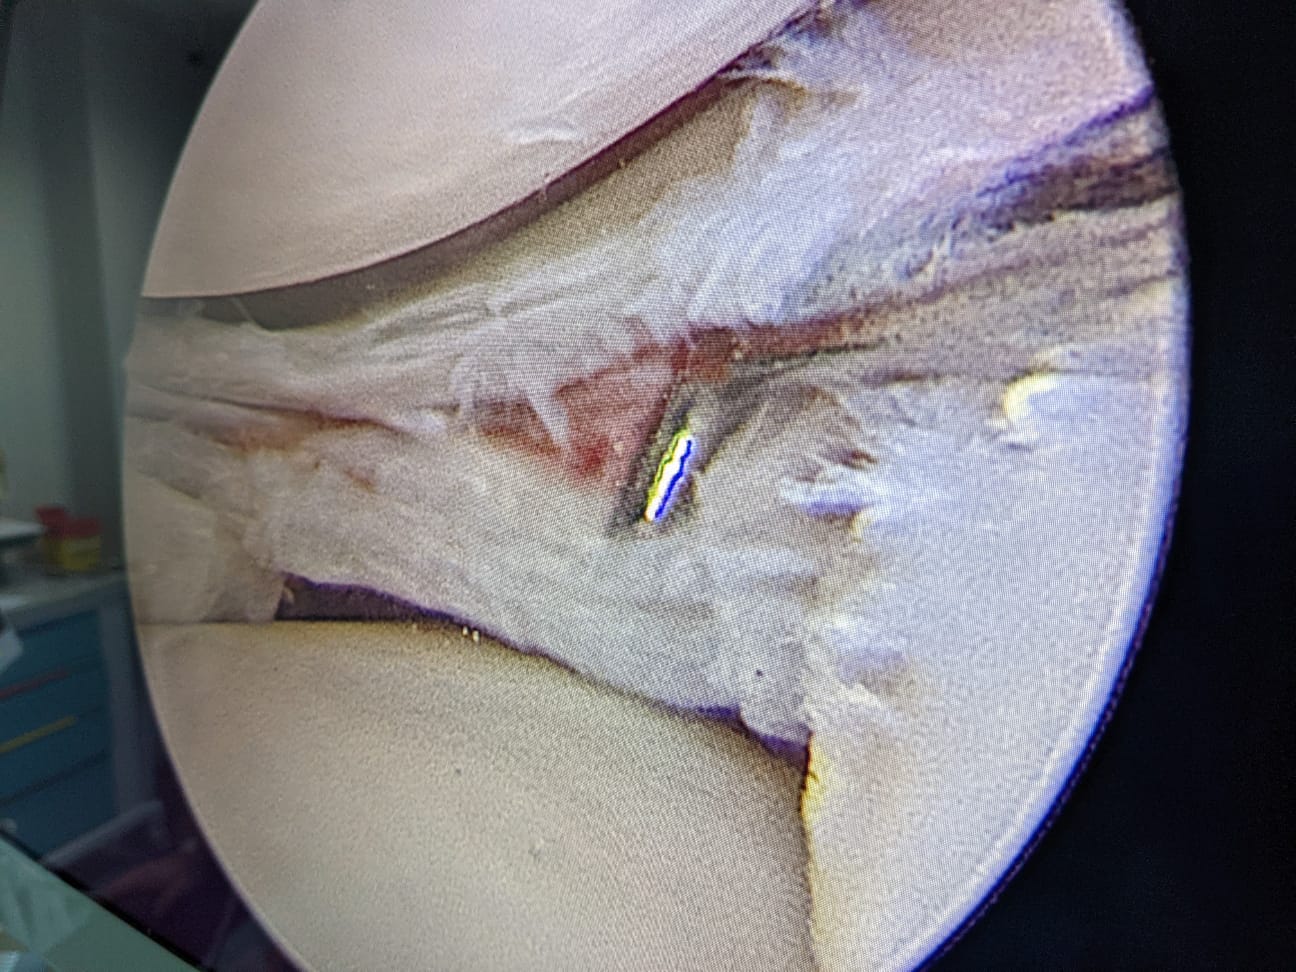

“Pacientul a suferit leziune gravă de menisc extern subluxantă, în langhetă, de corn posterior în totalitate și clivaj orizontal al părții medii meniscale externe. Am efectuat sutura de menisc extern, corn posterior, cu 2 ancore (prin tehnică în lasou) și partea medială, pentru ruptura veche în toartă de coș, ruptă după al doilea traumatism.

Procedura intervențională a fost minim-invazivă (laparoscopică), tehnica de sutură în lasou fiind ceea mai nouă și mai fiabilă (AOSS USA).

Așadar am ales tehnica chirurgicală de sutură a leziunilor complexe de menisc, pentru Theo Oprea, la care se adaugă protocolul francez de recuperare ameliorată, accelerată după chirurgia osteo-articulară, propus și practicat de mine în acest caz, după informarea consimțită a pacientului, despre beneficiile, riscurile și eventualele complicații ale acestui tip de intervenție chirurgicală, cu asumarea comună, pe baza unor scoruri de evaluare, pre și post-operatorie”.